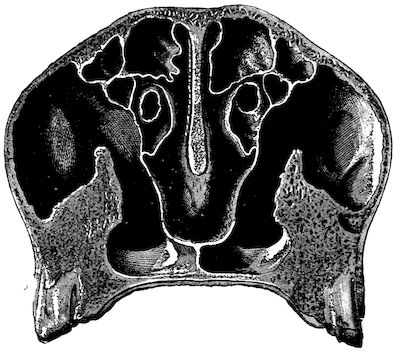

Fig. 8.—Transverse section through the middle region of the face in a pig suffering from osseous cachexia.

18In the final stages, the bones may be cut with a knife, and a time arrives when bony tissue seems completely to have disappeared; thus, as shown in Fig. 8 herewith, it was possible to cut the entire head of a pig into thin slices without the slightest difficulty. All parts of the head had been affected by the softening change.

From the chemical point of view, the diminution in mineral salts and in phosphate of calcium has long been recognised, but the degree of this change varies according to the phase. In human beings the proportions have been estimated as follows: Normal bone, 50 to 80 per cent. of phosphate of calcium; bone in persons suffering from osteomalacia, 5 to 20 per cent. of phosphate of calcium. The changes in the ossein have not been carefully studied. We only know that histologically the ossein becomes fibrillar, and that chemically it no longer retains its normal composition.